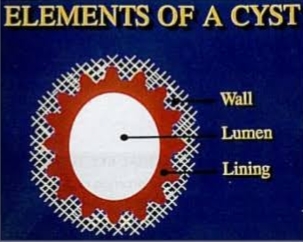

The wall of the capsule is composed of the collagenous fibrous connective tissue usually within epithelial lining and it produces various bond reserving factors for its growth and expansion .

PARTS OF A CYST : Cyst has following parts: -> WALL (made of connective tissue) -> EPITHELIAL LINING. -> LUMEN OF CYST